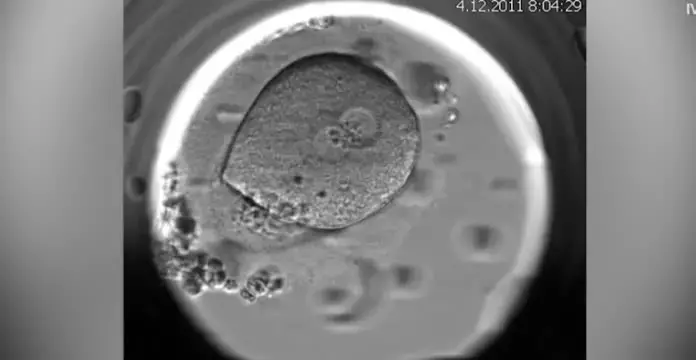

실제 실험에서, 이렇게 만들어진 82개의 인공 난자를 수정시킨 결과, 약 9%가 초기 배아 단계인 '배반포'까지 성공적으로 발달했다고 합니다.

▪ 안전성 문제 : 성공적으로 발달한 소수의 배아에서도 '염색체 이상'이 발견되었습니다.